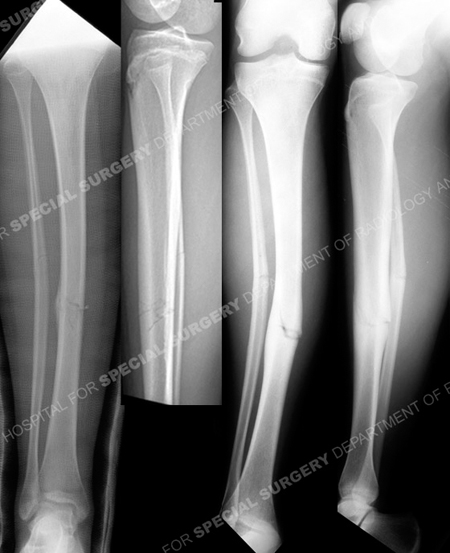

Anteroposterior (AP) and lateral radiographs (left images) reveal a minimally displaced mid-shaft tibia stress fracture. AP and lateral radiographs at 6 months following the injury (right images) illustrating a malunion with 13° of valgus deformity.